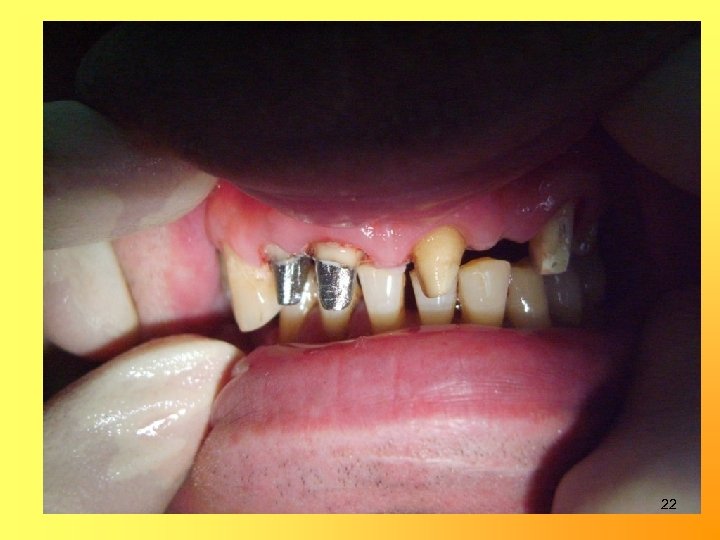

21

22

Изготовление металлокерамических мостовидных протезов и коронок 1, 5 -2, 0 мм 1, 0 -1, 5 мм 1, 0 мм 24